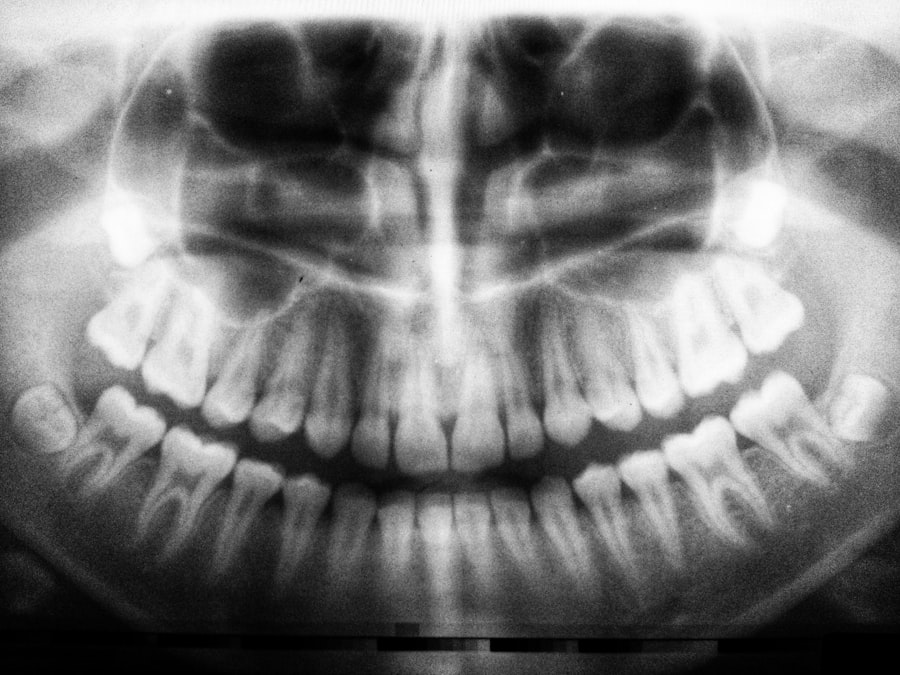

Tooth decay under a crown that has undergone a root canal can be a perplexing issue for many. When you have a root canal, the goal is to remove the infected pulp from the tooth, clean the interior, and seal it to prevent further infection. After this procedure, a crown is often placed to restore the tooth’s structure and function.

However, even with these protective measures, decay can still occur beneath the crown. This situation arises when bacteria manage to infiltrate the tooth structure, often due to a compromised seal or damage to the crown itself. Understanding how decay can develop under a crown is crucial for maintaining your oral health.

The crown serves as a barrier, but it is not impervious. Over time, the materials used in dental crowns can wear down, leading to gaps that allow bacteria to enter. Additionally, if the tooth was not adequately cleaned during the root canal procedure or if there are pre-existing conditions like gum disease, the risk of decay increases significantly.